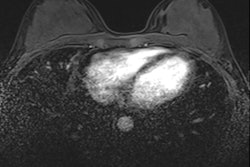

A 57-year-old woman was referred from a private clinic for an ill-defined irregular mass in the right breast, enhancing on both CESM and MRI (circles). CESM also showed diffuse enhancement throughout the left breast, for which random biopsies were taken, showing lobular carcinoma in situ (LCIS). Because of its extent, an MR-guided biopsy was recommended by the multidisciplinary team, again showing LCIS. Based on these findings and the patient's preference, a bilateral mastectomy with reconstruction was performed. Final pathology showed invasive carcinoma of no special type in the right breast, but 10 invasive lobular cancer foci varying from 3 mm to 10 mm in the left breast surrounded by LCIS. Images courtesy of Dr. Marc Lobbes."I think it is the combination between your mammographic image (in which you can appreciate the morphology of lesions very well through the high spatial resolution) and the enhancement seen on the recombined images," he told ECR Today. "On MRI, especially with small foci, you see them enhancing, but because of the spatial resolution, it is much more difficult to appreciate the subtle morphology."